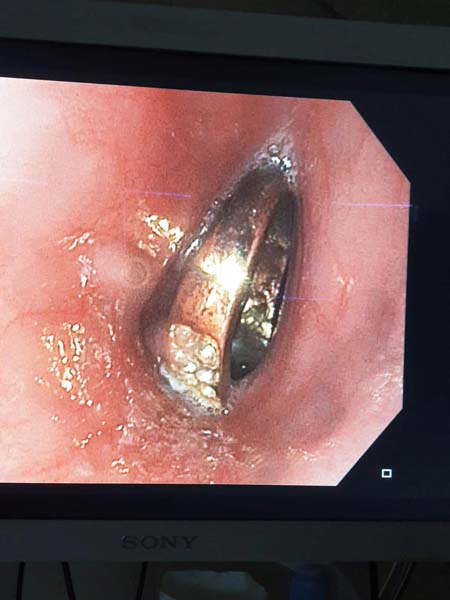

نجح الطاقم الطبي في مستشفى زيف في صفد ، في استخراج خاتم من داخل مريء طفلة ( 6 سنوات ) ، وذلك بعد اجراء عملية لها واخضاعها للتخدير الكلي .

وقد حذّر دكتور بيان هنو الذي أجرى العملية بنجاح من تكرار هذه الحالات ، وطلب من الأهل الانتباه لأولادهم وذلك في اعقاب تكرار مثل هذه الحوادث ، حيث تم قبل اسبوع اخراج مشبك شعر من بطن طفل في الثالثة من عمره بعد ان قام بابتلاعه .

وافاد مستشفى زيف في صفد ان" العملية التي اجريت للطفلة سمحا سويسا من صفد تعتبر بمثابة انقاذ لحياتها وذلك بعد ان ابتلعت الخاتم المرصع بالمجوهرات وشعرت باوجاع في منطقة الصدر، فتم نقلها الى مستشفى زيف في صفد وبعملية حذرة جدا من اجل عدم جرح ألأعضاء الداخلية للطفلة ، تم استخراج الخاتم بنجاح وتسريح الطفلة في اليوم التالي وهي بصحة جيدة " .